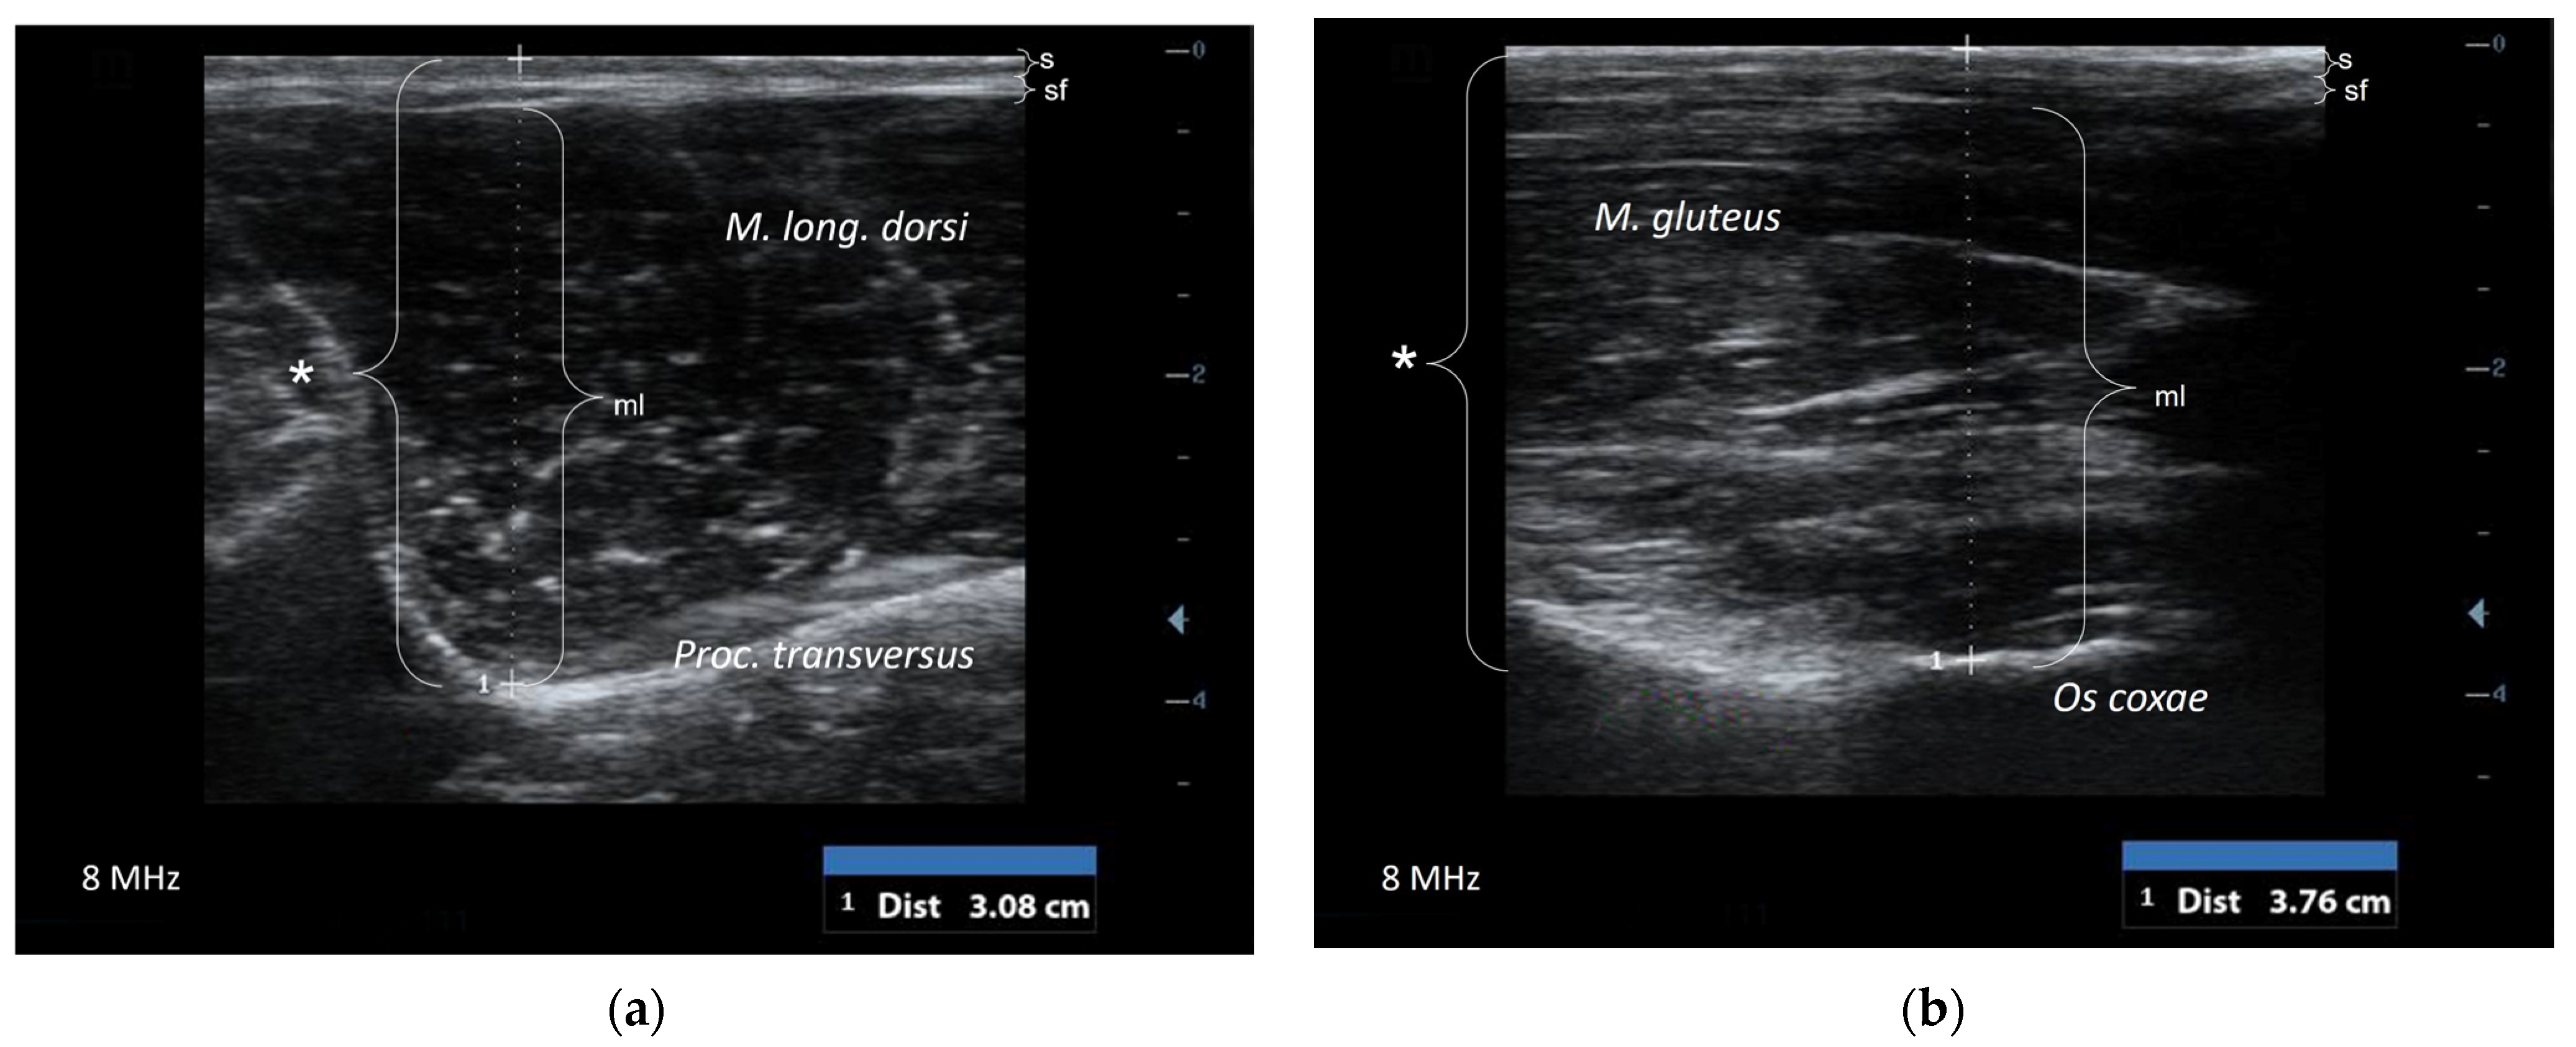

2.3. Ultrasonographic Examination